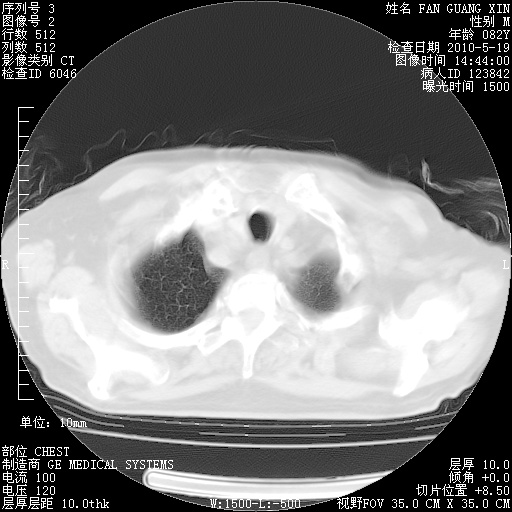

复查肺部CT,明显好转。为什么发热呢?

治疗3周后的肺部CT

治疗3周后的肺部CT纵隔窗